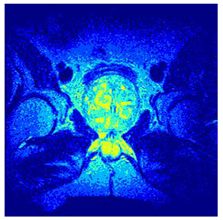

| Image | nt = 3 | nt = 4 | nt = 5 | nt = 8 |

|---|---|---|---|---|

| 1 | ![]() | ![]() | ![]() | ![]() |

| 2 | ![]() | ![]() | ![]() | ![]() |

| 3 | ![]() | ![]() | ![]() | ![]() |

| 4 | ![]() | ![]() | ![]() | ![]() |

| 5 | ![]() | ![]() | ![]() | ![]() |

| 6 | ![]() | ![]() | ![]() | ![]() |

| 7 | ![]() | ![]() | ![]() | ![]() |

| 8 | ![]() | ![]() | ![]() | ![]() |

| 9 | ![]() | ![]() | ![]() | ![]() |

| 10 | ![]() | ![]() | ![]() | ![]() |

| 11 | ![]() | ![]() | ![]() | ![]() |